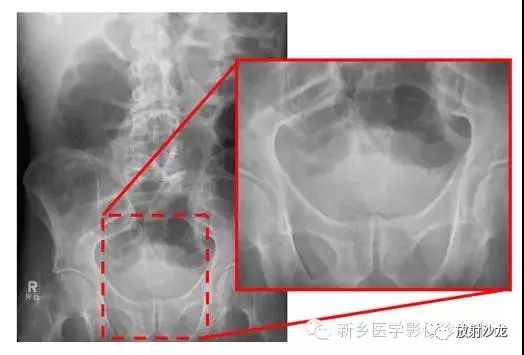

腹痛患者所做的腹部平片。有助于临床诊断的微妙征象是什么呢?

气腹患者摩里逊陷凹存在气体。平片中,靠近11肋的右上象限可见三角形(如在这种情况下)、半圆形,或月牙形的气体集聚。在仰卧位X光片中,右上象限的气体不能解释为肠道内气体,通常为腹腔内游离气体的最早迹象。

同一患者前-后坐位的胸片所示右膈下(箭头)游离气体,证实了气腹的诊断。